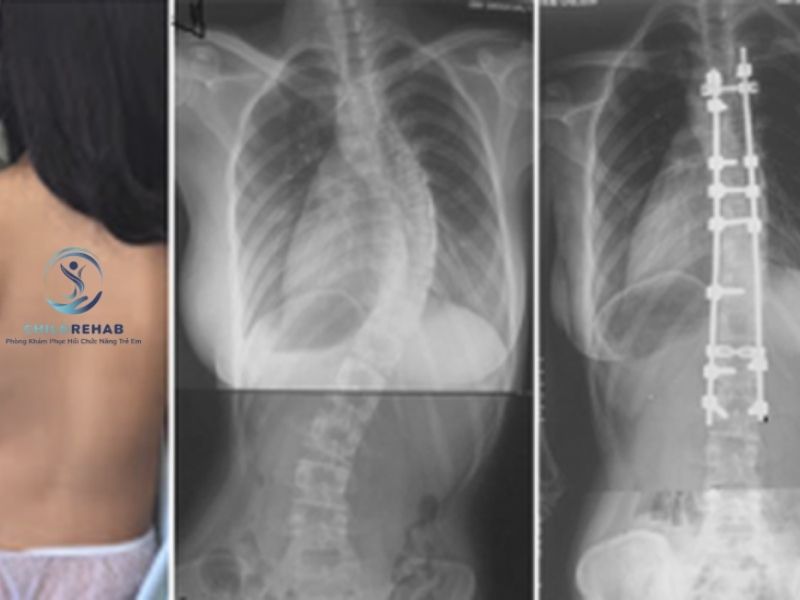

Không phải trường hợp nào trẻ bị cong vẹo cột sống cũng cần chụp X-quang. Tìm hiểu khi nào cần thêm đánh giá hình ảnh.

Tìm hiểu các hướng hỗ trợ và điều trị cong vẹo cột sống ở trẻ tùy theo nguyên nhân, mức độ và độ tuổi phát triển.

Trẻ bị cong vẹo cột sống có phải mổ không? ChildRehab giúp phụ huynh hiểu đúng về mức độ và hướng xử lý phù hợp.